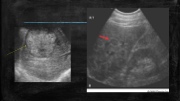

Page 18 - SONO 260 Patologías Hígado - PC2